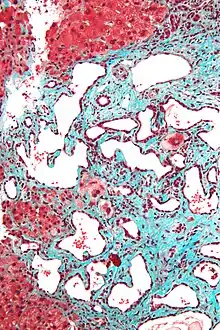

Micrograph of a bile duct hamartoma. Trichrome stain. Intermediate magnification

Micrograph of a bile duct hamartoma. Trichrome stain. Intermediate magnification Micrograph of a bile duct hamartoma. Trichrome stain, high magnification